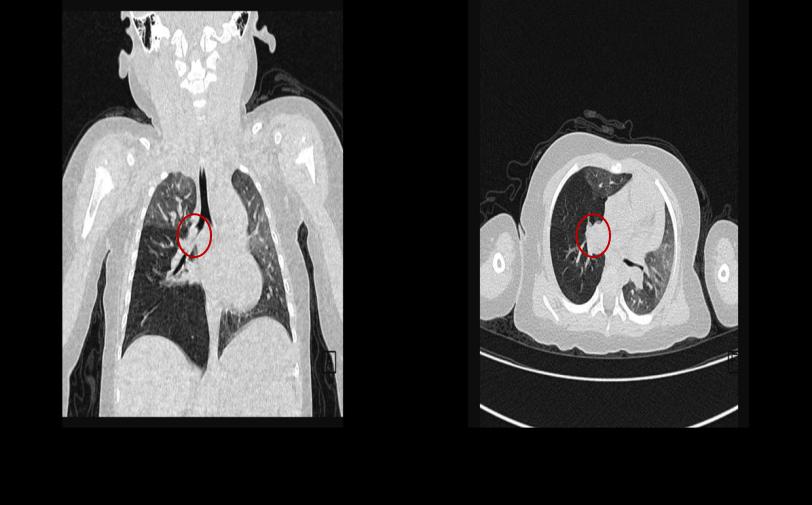

2024年2月29日下午,西安交通大学第二附属医院儿科呼吸病区收治了一名1岁3个月因误食“瓜子”后出现喘息的患儿,入院后紧急行胸部CT及支气管三维重建,发现右肺中间段支气管可见一高密影(图1),结合病史考虑支气管异物,由于患儿年龄小,气道窄,且嵌顿位置位于右肺中间段支气管开口处,取出难度大,侯伟教授立即组织呼吸专业全体医生进行充分术前讨论,为患儿制定最优的介入手术方案。